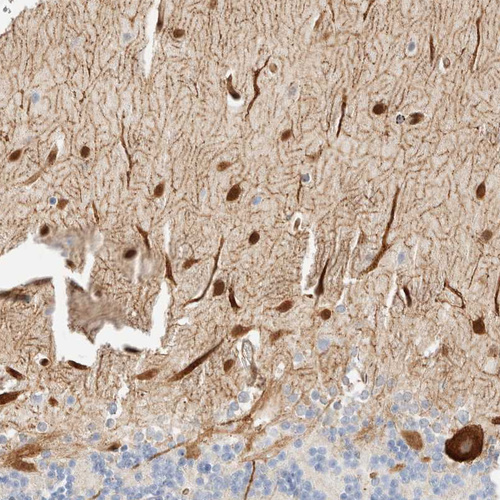

Immunohistochemistry analysis in human skeletal muscle and liver tissues using HPA024059 antibody. Corresponding LMCD1 RNA-seq data are presented for the same tissues.